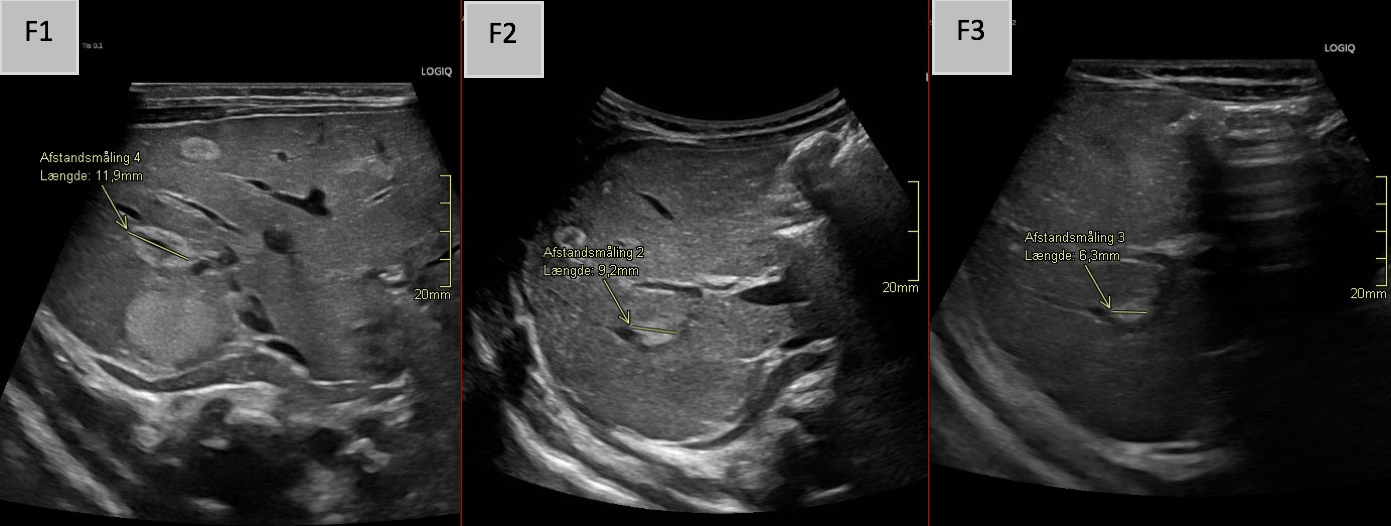

F 1-3: Axial B-mode images from the initial examination and follow-up scans at approximately 4 and 12 weeks, demonstrating shrinkage of a monitored hepatic hemangioma from 12 mm initially to 9 mm and finally 6 mm.

A lesion with heterogeneous echogenicity – most consistent with a splenic hemangioma- was also identified in the spleen (E). Follow-up ultrasound examination demonstrated rapid regression of the HH (F2-3).

Follow-up ultrasound exams showed significant reduction in the HH's size and number, supporting a conservative management strategy for this clinically stable patient.